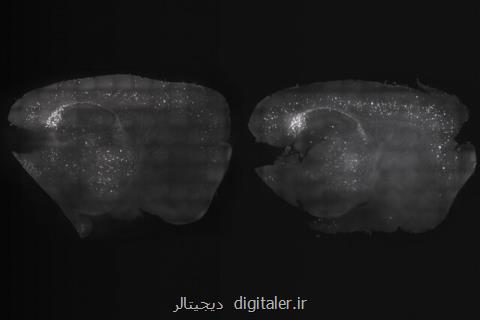

به گزارش دیجیتالر به نقل از ایسنا و به گزارش ام. آی. تی نیوز، متخصصان علوم اعصاب دانشگاه "ام. آی. تی"(MIT) با قرار دادن موش ها در معرض تركیب منحصر به فردی از نور و صدا، نشان دادند كه امكان بهبود نقص های شناختی و حافظه این موجودات وجود دارد. شاید نتایج این بررسی بتوانند به بهبود بیماران مبتلا به آلزایمر كمك كنند.

این درمان غیرتهاجمی كه امواج مغزی را تحت تأثیر قرار می دهد، "نوسانات گاما"(gamma oscillations) نام دارد و می تواند تعداد پلاك آمیلوئید(عامل اصلی آلزایمر و تخریب سلول های عصبی) را در مغز موش ها كم كند. پلاك های آمیلوئید، در مغز به خصوص در نواحی از مغز كه بر فعالیت هایی مانند یادگیری و حافظه تأثیر دارند، ایجاد می شوند.

پژوهشگران در آزمایش جدید خود با استفاده از محرك صوتی، امكان دسترسی به نواحی گوناگون مغز را بررسی كردند و دریافتند قرار گرفتن در معرض میزان مشخصی از صدا در هر روز و تكرار این فرآیند به مدت یك هفته، می تواند میزان آمیلوئید را در قشر شنوایی مغز كه مسئول پردازش صداست، كم كند.

"لی هویی تسای"(Li-Huei Tsai)، از نویسندگان این پژوهش اظهار داشت: هنگامی كه محرك های دیداری و شنیداری را به مدت یك هفته تركیب كردیم، شاهد نقش قشر پیش پیشانی و كاهش شگفت انگیز آمیلوئیدها بودیم.